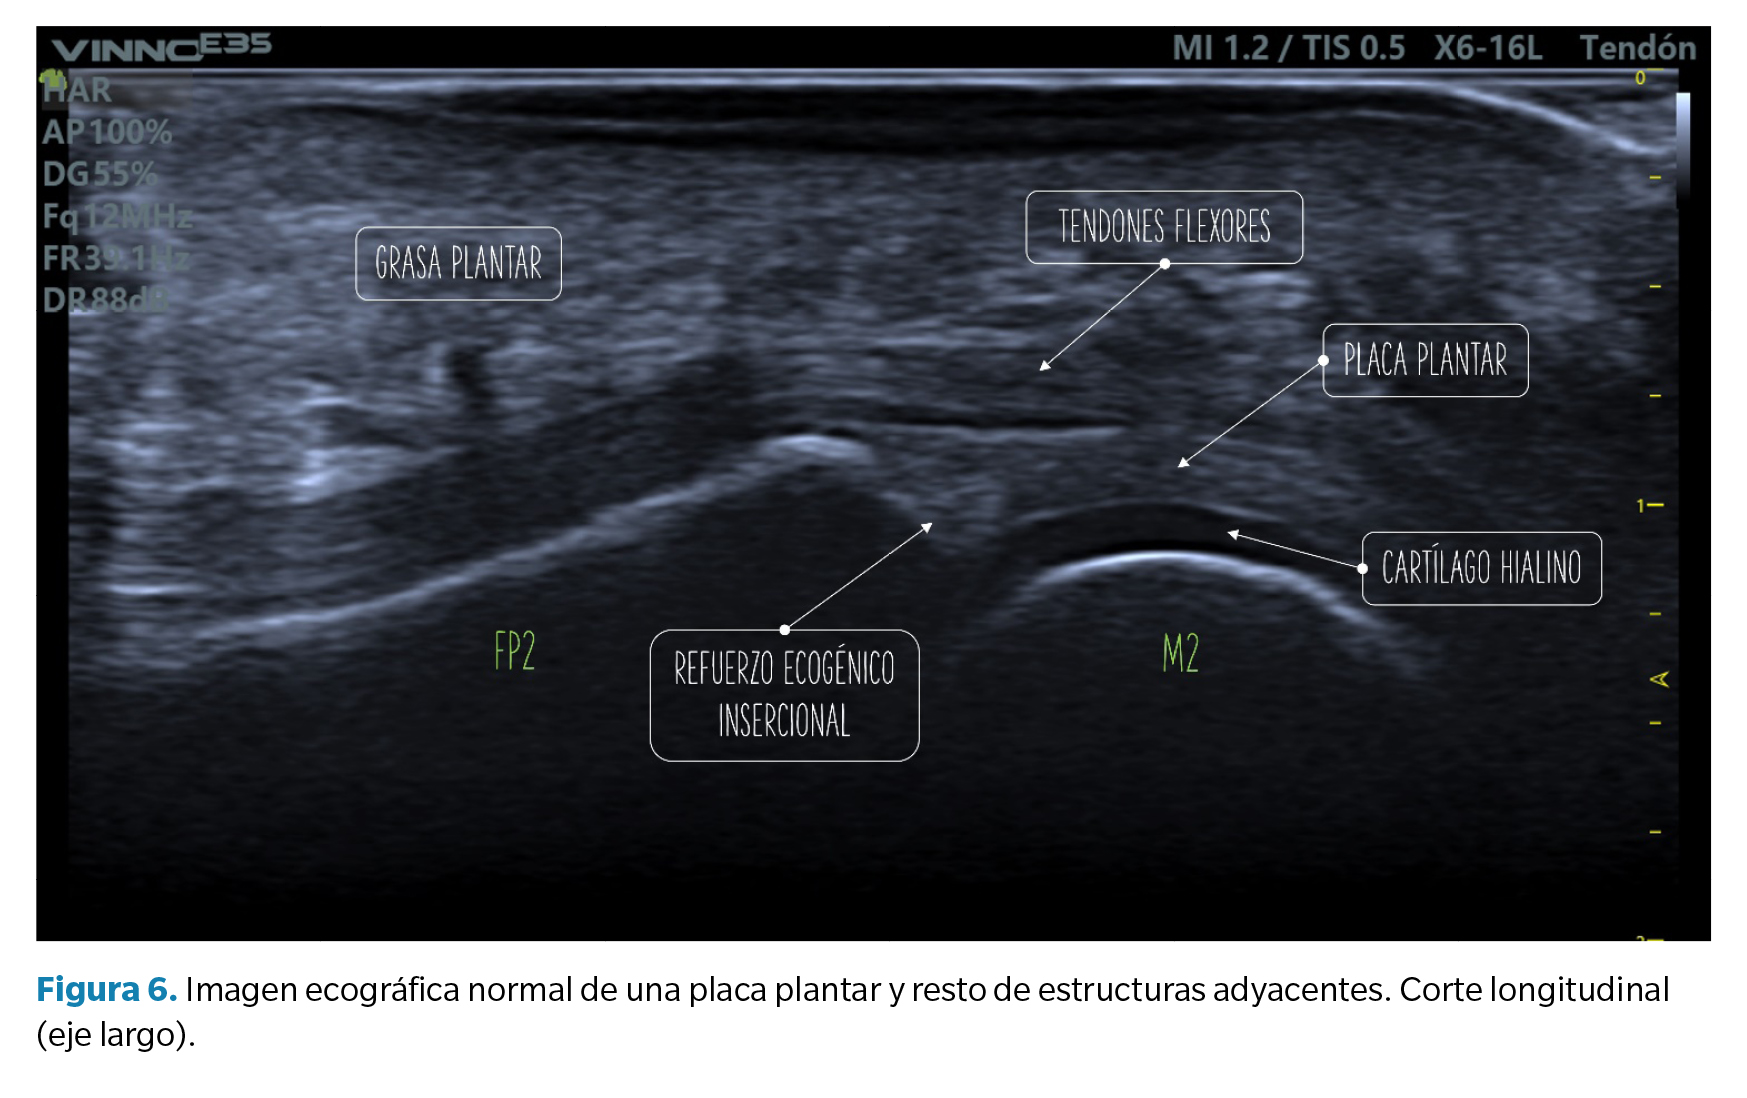

Criterios de normalidad de la imagen ecográfica

- Corte longitudinal (eje largo): la placa plantar normal se muestra ecográficamente como una estructura curvilínea ligeramente ecogénica con ecotextura granulada homogénea. Esta textura permite la diferenciación, no siempre definida, con los tendones flexores subyacentes de textura fibrilar. La superficie articular de la placa se define con precisión limitando con el cartílago hialino de la cabeza metatarsal, hipoecoico (Figura 6).

En la unión con la falange proximal, bien definida, el contorno óseo es normalmente liso y en la placa puede aparecer una zona triangular más ecogénica que se ha descrito como un hallazgo ecográfico normal y podría representar una mayor proporción de fibras de colágeno. La unión proximal al cuello metatarsal, en cambio, tiene una definición pobre en imagen ecográfica (Figura 6).